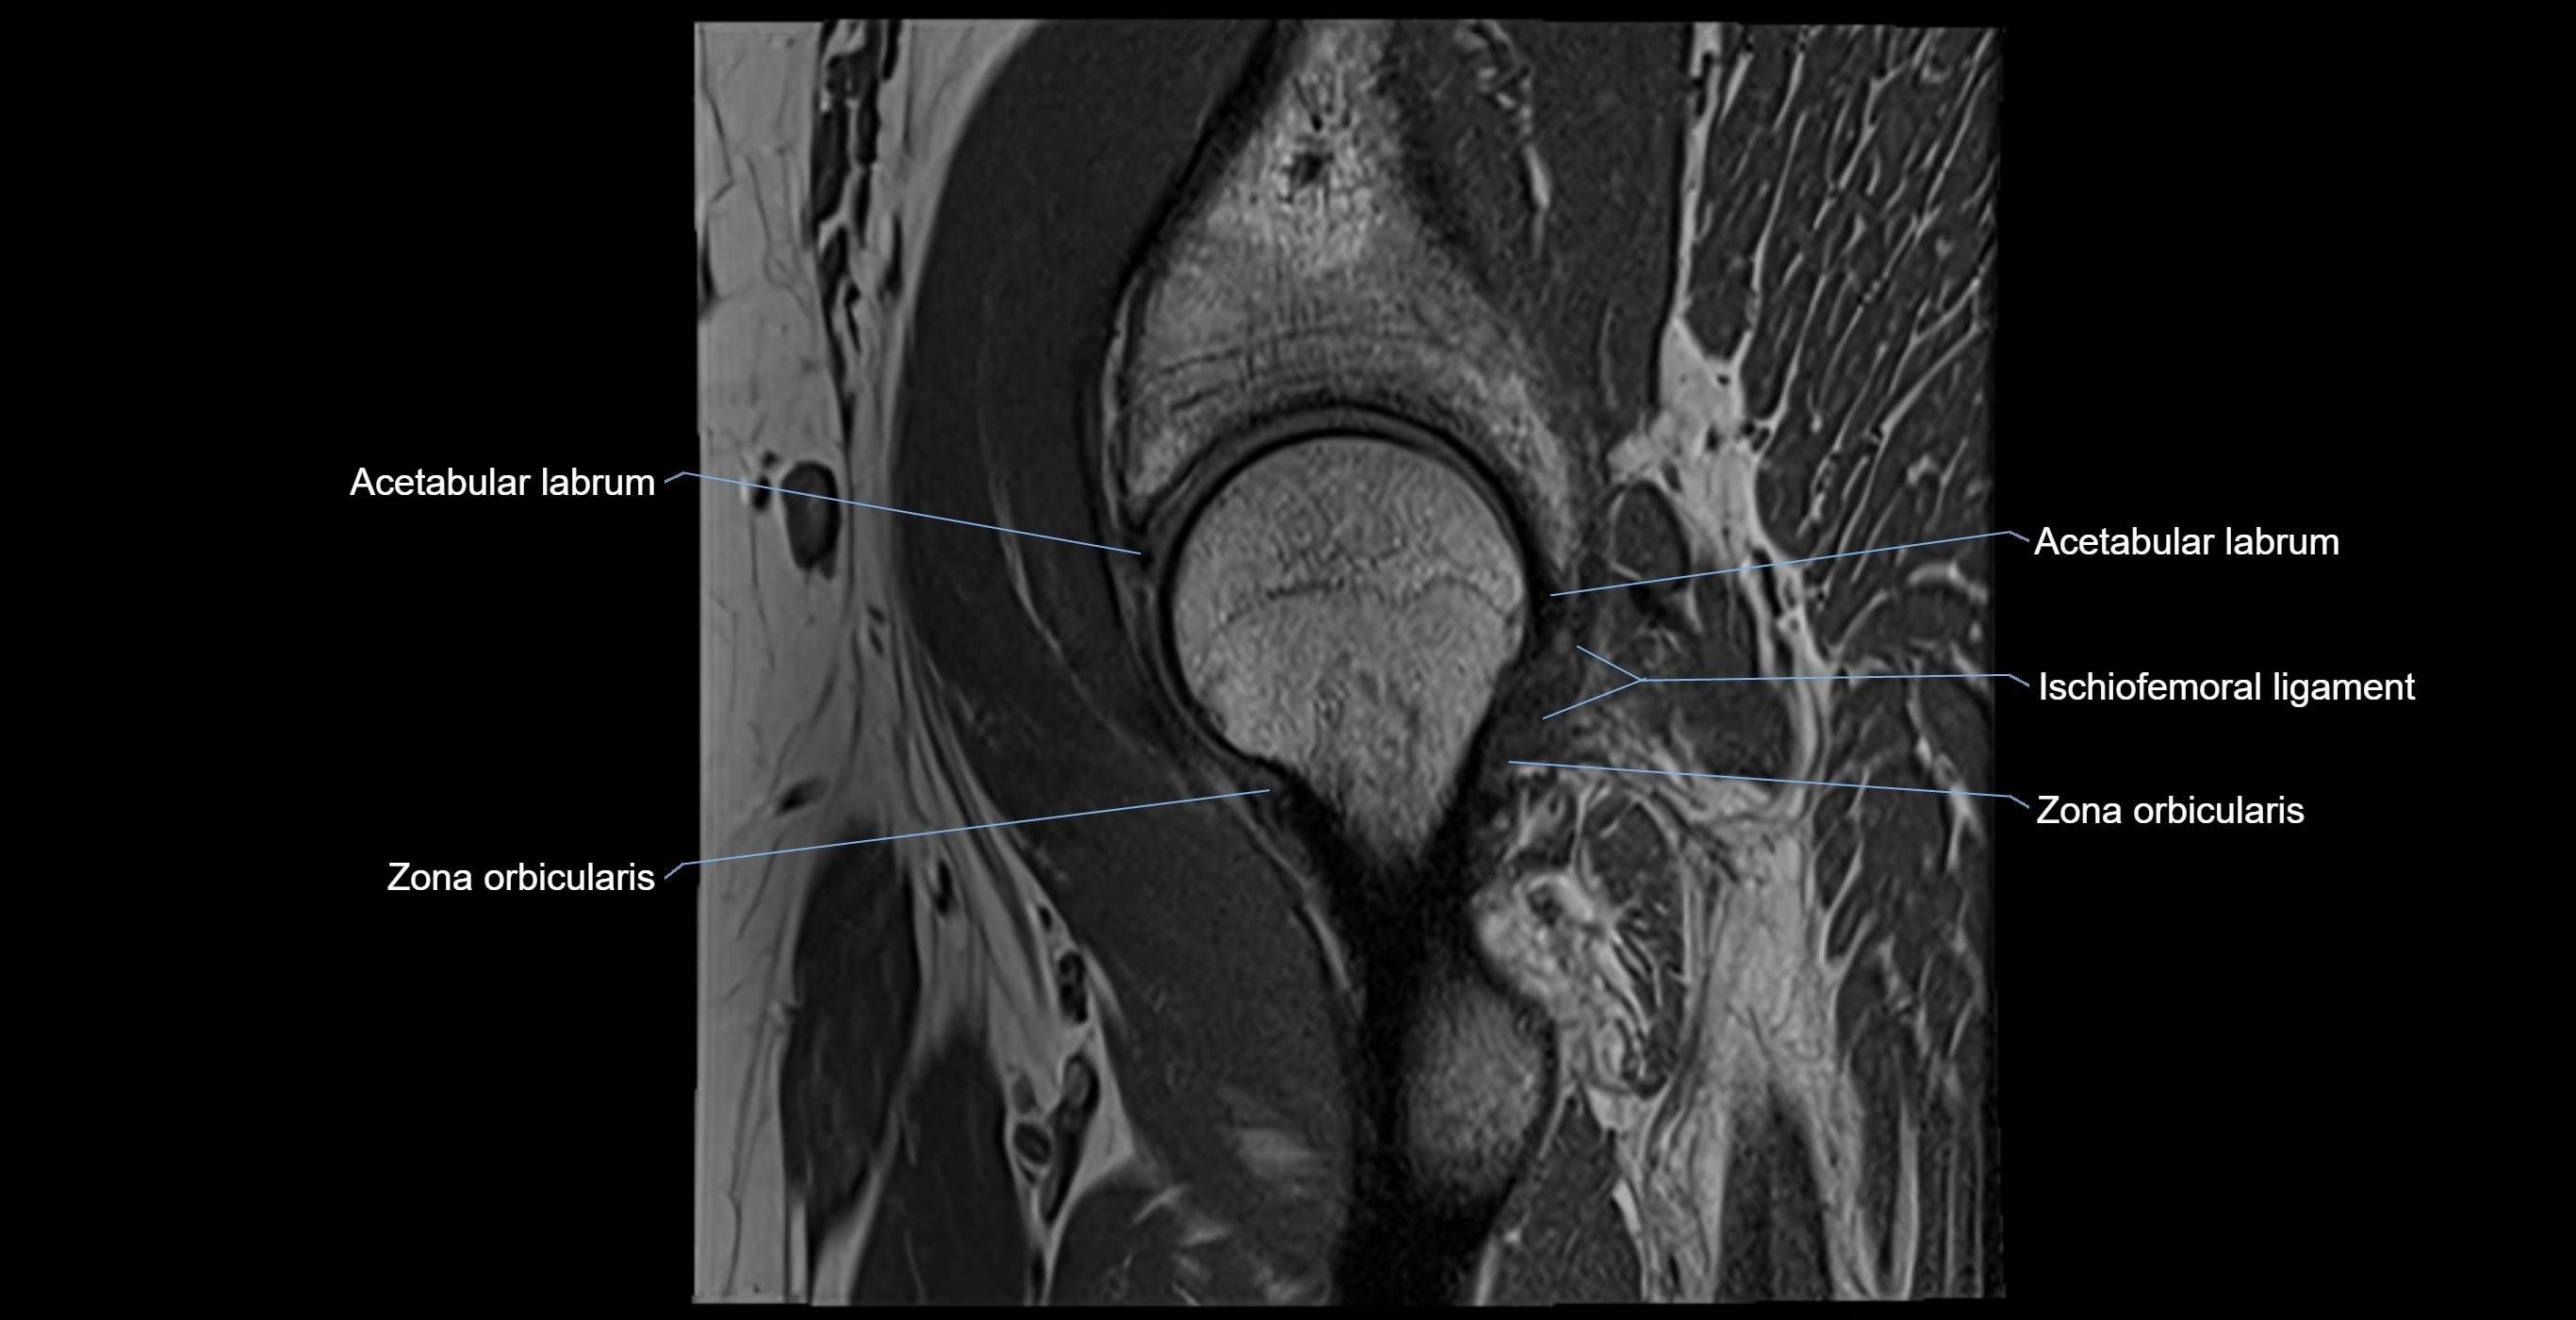

MRI image

image

MRI Appearance

T2-weighted images:

• Labrum: low signal intensity (dark)

• Joint fluid: bright, making labral tears visible as fluid extending into or around labrum